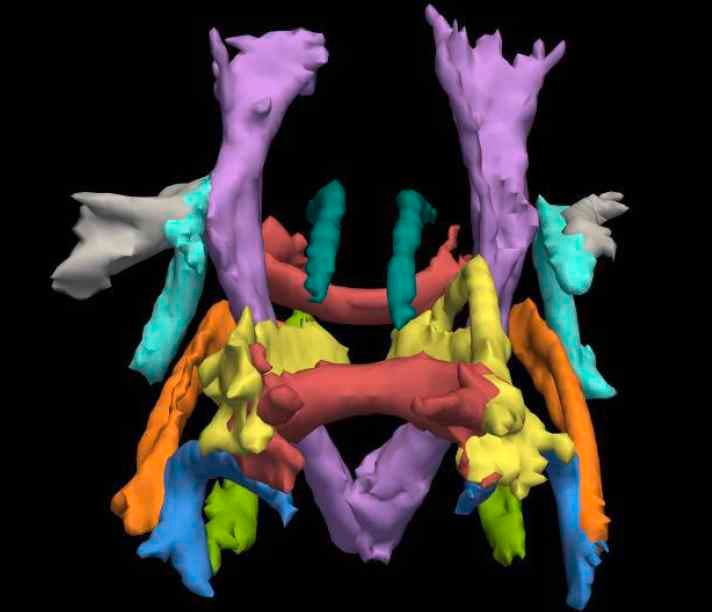

We provide the capability to investigate a wide range of clinical conditions using magnetic resonance imaging (MRI), Positron Emission Tomography (PET), electroencephalography (EEG) and transcranial brain stimulation. We have particular expertise in neuroscience and oncology, as well as multimodal imaging. We are part of the Department of Medicine at Imperial and are located at the Hammersmith Hospital, benefiting from the Hospital’s long tradition of world-class imaging research.

Magnetic Resonance Imaging (MRI)

The Siemens 3T Verio MRI scanner comprises a 70cm diameter open-bore, short-axis magnet. It has been equipped with a comprehensive range of transmit/receive coils suitable for many body regions and applications. The relatively large bore (compared to most MRI systems) ensures a higher degree of subject comfort and compliance.